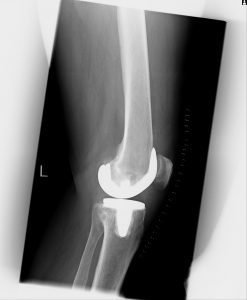

(Bilder unten: Totalendoprothese Kniegelenk)